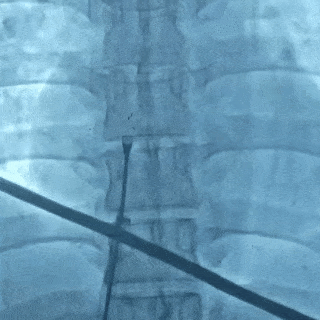

释放封堵器

钢缆和鞘管同时撤出,成功释放封堵器

术后超声

超声下可见封堵器左右盘面牢牢贴靠房间隔,且无残余分流,封堵成功